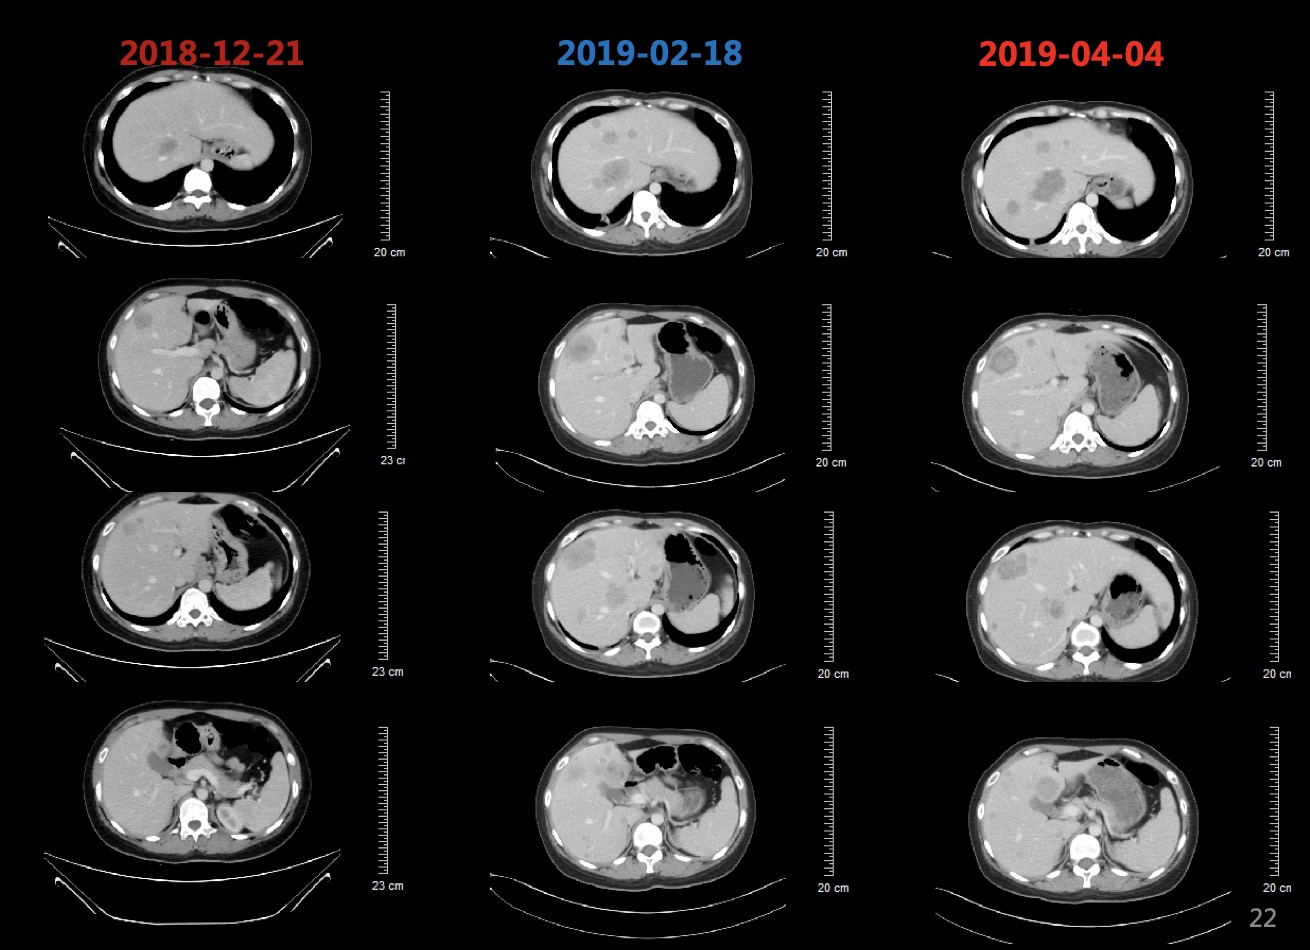

患者于2018-12-26、2019-01-19分别行第1-2周期TC方案(紫杉醇脂质体+卡铂,每3周1次),患者基线和化疗后肿瘤标志物变化如图3所示,肺和肝脏病灶变化影像如图4所示,2019-02-18复查CT提示肺部病灶稳定(缩小),肝脏病灶增多增大,总体疗效评价疾病进展(PD)。

图4 患者基线和化疗后肺部病灶和肝脏病灶对比影像,肺部病灶缩小,肝脏病灶增多增大

2019-02-19、2019-03-14行二线贝伐珠单抗+多西他赛化疗(贝伐珠单抗+多西他赛,每3周1次)。2019-03患者开始出现腰部疼痛,考虑为L1椎体骨转移导致,2019-03-19开始行腰骶部局部放疗,2019-04-04复查CT结果如图5所示,肺部病灶稳定(部分缩小),肝脏病灶增多增大、T9-T12椎体新发转移瘤,总体疗效评价(PD)。

图5 2019-04-04复查胸腹部CT结果影像,结果显示肺部病灶稳定(部分缩小),肝脏病灶增多增大、T9-T12椎体新发转移瘤

患者初治时行PD-L1(22C3)检测提示PD-L1高表达为95%,故建议患者行三线免疫治疗。由于药物可及性,患者综合考虑后,选择信迪利单抗。患者于2019-04-04、2019-04-26、2019-05-18分别行第1~3周期免疫联合化疗三线方案(信迪利单抗+白蛋白紫杉醇 ,每3周1次)。2019-05-18复查肺部CT如图6所示,2019-05-18复查CT:肺部病灶较前明显缩小,阻塞性肺炎较前好转、肝脏病灶较前明显缩小。T2、T9-L2椎体及L2左侧附件多发骨转移同前。

图6 2019-05-18复查胸腹部CT提示肺部病灶较前明显缩小,阻塞性肺炎较前好转、肝脏病灶较前明显缩小。T2、T9-L2椎体及L2左侧附件多发骨转移基本同前